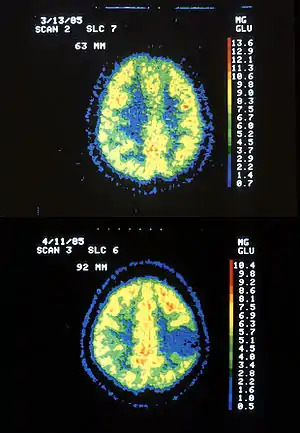

![]() | |

| Two PET images—the upper of which shows a normal brain and the lower shows astrocytoma. | |